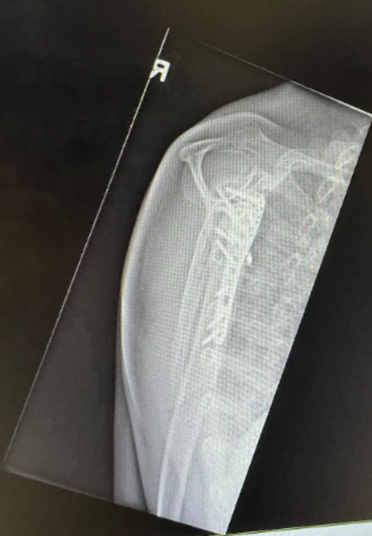

The patient underwent open reduction internal fixation (ORIF) on post-injury day 11. Following a deltopectoral approach and biceps tenodesis, the 4-part PHFD was seen. The humeral head was posteriorly dislocated and impacted upon the posterior glenoid with a nondisplaced head split. The greater tuberosity fragment was identified with an intact supraspinatus However there was an avulsion of the subscapularis off the lesser tuberosity. The humeral head was reduced with judicious soft tissue management and assessed in-situ to prevent secondary injury and ischemia. The articular block was secured with 2 headless compression screws. The neck-shaft angle was restored using plate-assisted reduction and an angular stable construct was achieved with an anatomical locking compression plate (Synthes PHILOSTM). To prevent varus malunion, the height of the plate was determined on fluoroscopy (Image 2) to enable the inferomedial ‘kickstand’ screw [31]. The medial calcar was reduced and cerclaged to the plate for bony apposition and increased fixation strength. Cement augmentation (Stryker Hydroset) was performed. Transosseous repair of the Subscapularis was done with closure of the rotator interval.

Image 2: Intraoperative fluoroscopy demonstrating satisfactory anatomical reduction of the 4-part proximal humeral posterior fracture-dislocation.

Image 3: Immediate postoperative radiographs of the right shoulder.

Image 4. 5: Month follow-up radiograph of the right shoulder demonstrating bridging callus and bony union.

The patient followed a structured rehabilitation program that progressed in alignment with key postoperative milestones (Table 1). Pendulum exercises were initiated in the early phase (week 3 post-op) to promote gentle mobility while respecting non-weight-bearing precautions.[33] By week 7, the patient progressed to passive and active-assisted ROM exercises, with particular emphasis on external rotation (Image 6) and flexion (Image 7) using cane-assisted techniques. [33,34] At this stage, the patient also returned to light-duty work. Due to reported stiffness during daily activities, external rotation mobility (Image 8) was further emphasized at the 3-month review. At week 12, the patient initiated active ROM with light resistance, including anterior press and pulley-based exercises. To address his persistent motion limitations, glenohumeral joint mobilization was introduced [35]. Radiographs at 5 months post-operation (Image 4) confirmed bony union, and by week 23, the patient had achieved full functional recovery, resumed cycling and daily activities, with continued education to avoid high overhead movements in view of rotator cuff muscle repair.

Postoperatively, the patient was started on pendular exercises for 6 weeks. before increasing to passive ROM at the postoperative 7 week. He was seen regularly at postoperative 2 weeks, 7 weeks, 3 months and 5 months. Patient returned to work while being placed on light duty at postoperative 7 weeks. On review at postoperative 3 months, there was an increased focus on external rotation range of motion exercises due to shoulder stiffness reported by the patient during daily activities. Bony union was observed on radiographs taken at postoperative 5 months (Image 4).